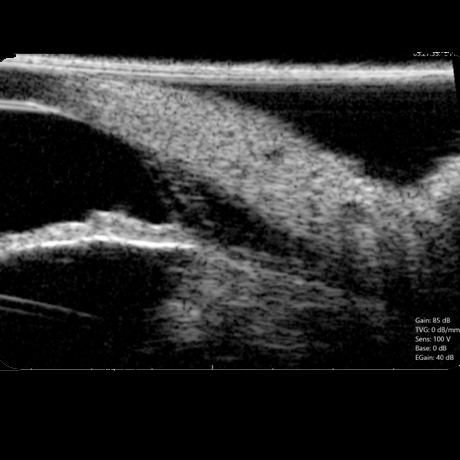

Na Oftalvet dispomos de equipamento avançado, de última geração, que permitem o diagnóstico das mais variadas doenças que afectam o globo ocular e seus anexos.